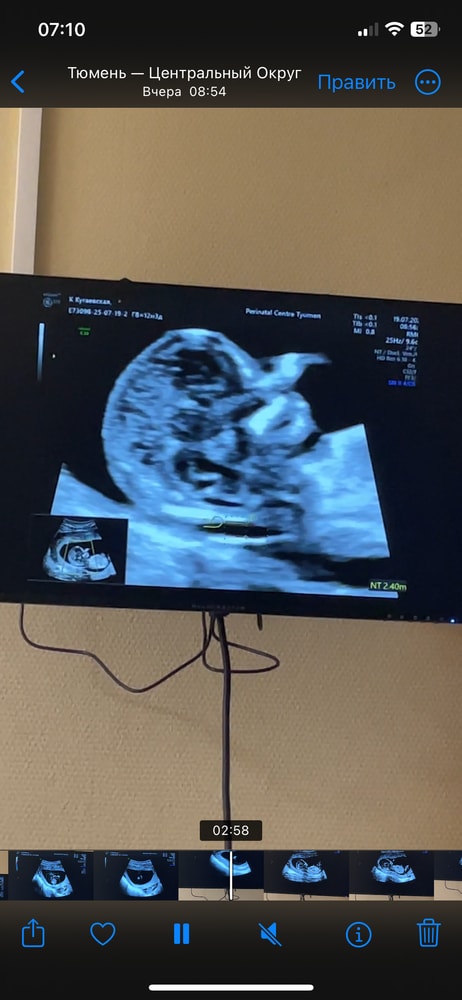

на 1 скрининге на сроке 12.4 недели

ктр 7,1см

Твп 2,8мм

срок по узи 13,2 недели.

все остальные показатели в норме. На узи напугали про твп чуть выше нормы.

Все измерения на фото скринах с узи. Не нашла вообще 2.8

Abigeil, просто странно, три раза намеряла 2,4. Потом один раз 2,7. В итоге написали 2,8